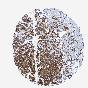

CANCER BREAST CANCER Show tissue menu

BRCA TCGA BRCA VALIDATION PROTEIN EXPRESSION

TMEM109 is not prognostic in Breast Invasive Carcinoma (TCGA)